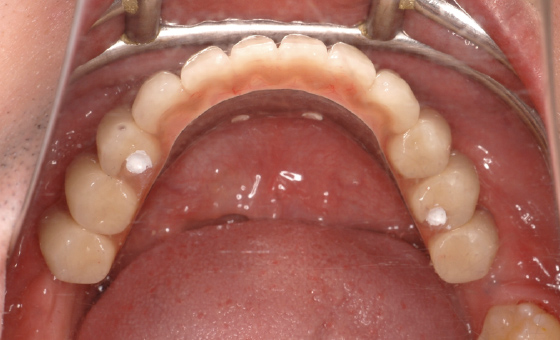

その後半年待ち、インプラントと骨がしっかりと結合したのちに最終的な人工歯を装着します。写真のように、バランスの取れた自然な清潔感あふれる笑顔が実現しました。